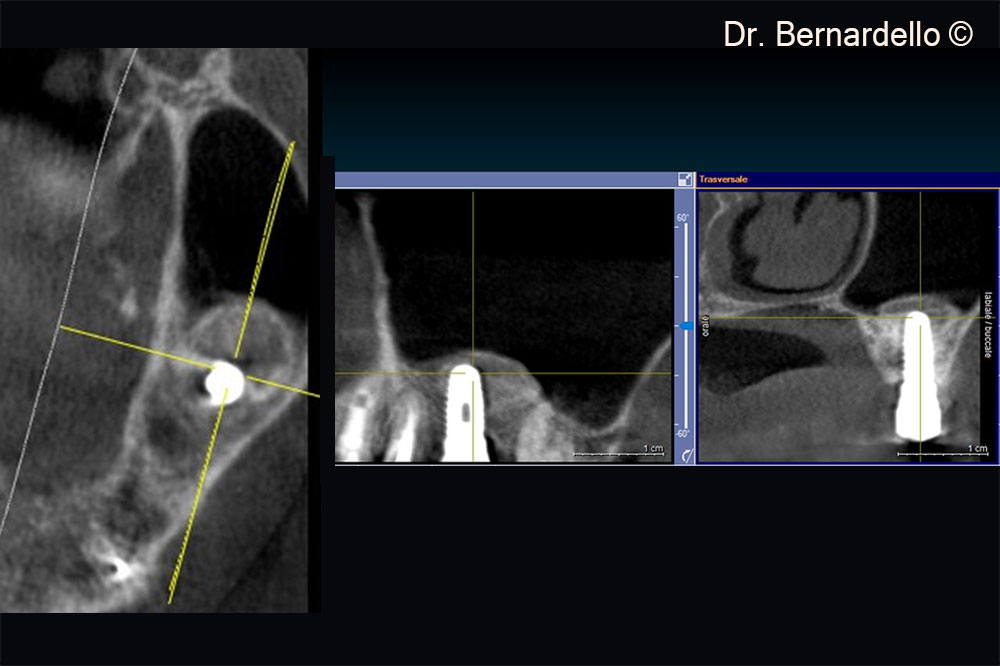

Based on sinus width, a female patient (55 years old) is considered eligible for a transcrestal sinus floor elevation

Based on the sinus width, the patient is considered eligible for a transcrestal sinus floor elevation